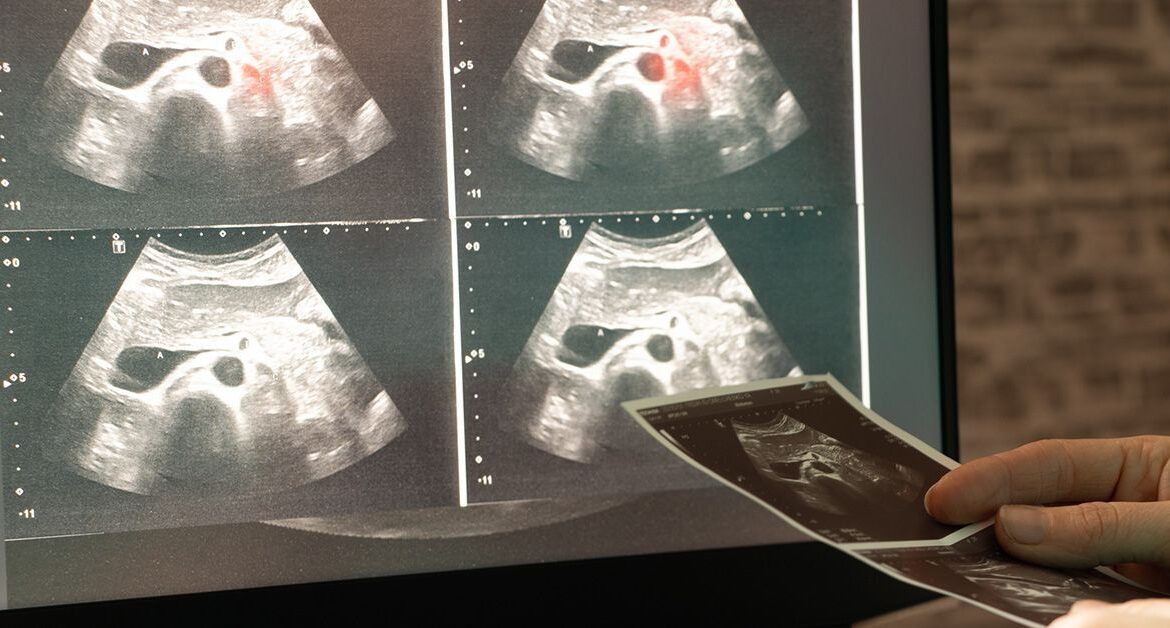

Công cụ AI này cải tiến một quy trình gọi là phân vùng ảnh y tế, trong đó mỗi điểm ảnh trong hình được gán nhãn — ví dụ, là mô ung thư hay mô bình thường. Trước đây, quy trình này thường do các chuyên gia giàu kinh nghiệm thực hiện. Tuy nhiên, các thuật toán học sâu đã cho thấy tiềm năng tự động hóa công việc vốn tốn nhiều công sức này.

Công cụ này đã được thử nghiệm trên nhiều loại hình ảnh y tế. Nó học cách nhận diện tổn thương da trên ảnh soi da, ung thư vú trên ảnh siêu âm, mạch máu nhau thai trên ảnh nội soi thai, polyp trên ảnh nội soi đại tràng, và loét bàn chân qua ảnh chụp thông thường. Phương pháp này cũng được mở rộng sang hình ảnh 3D, chẳng hạn lập bản đồ hồi hải mã hoặc gan.